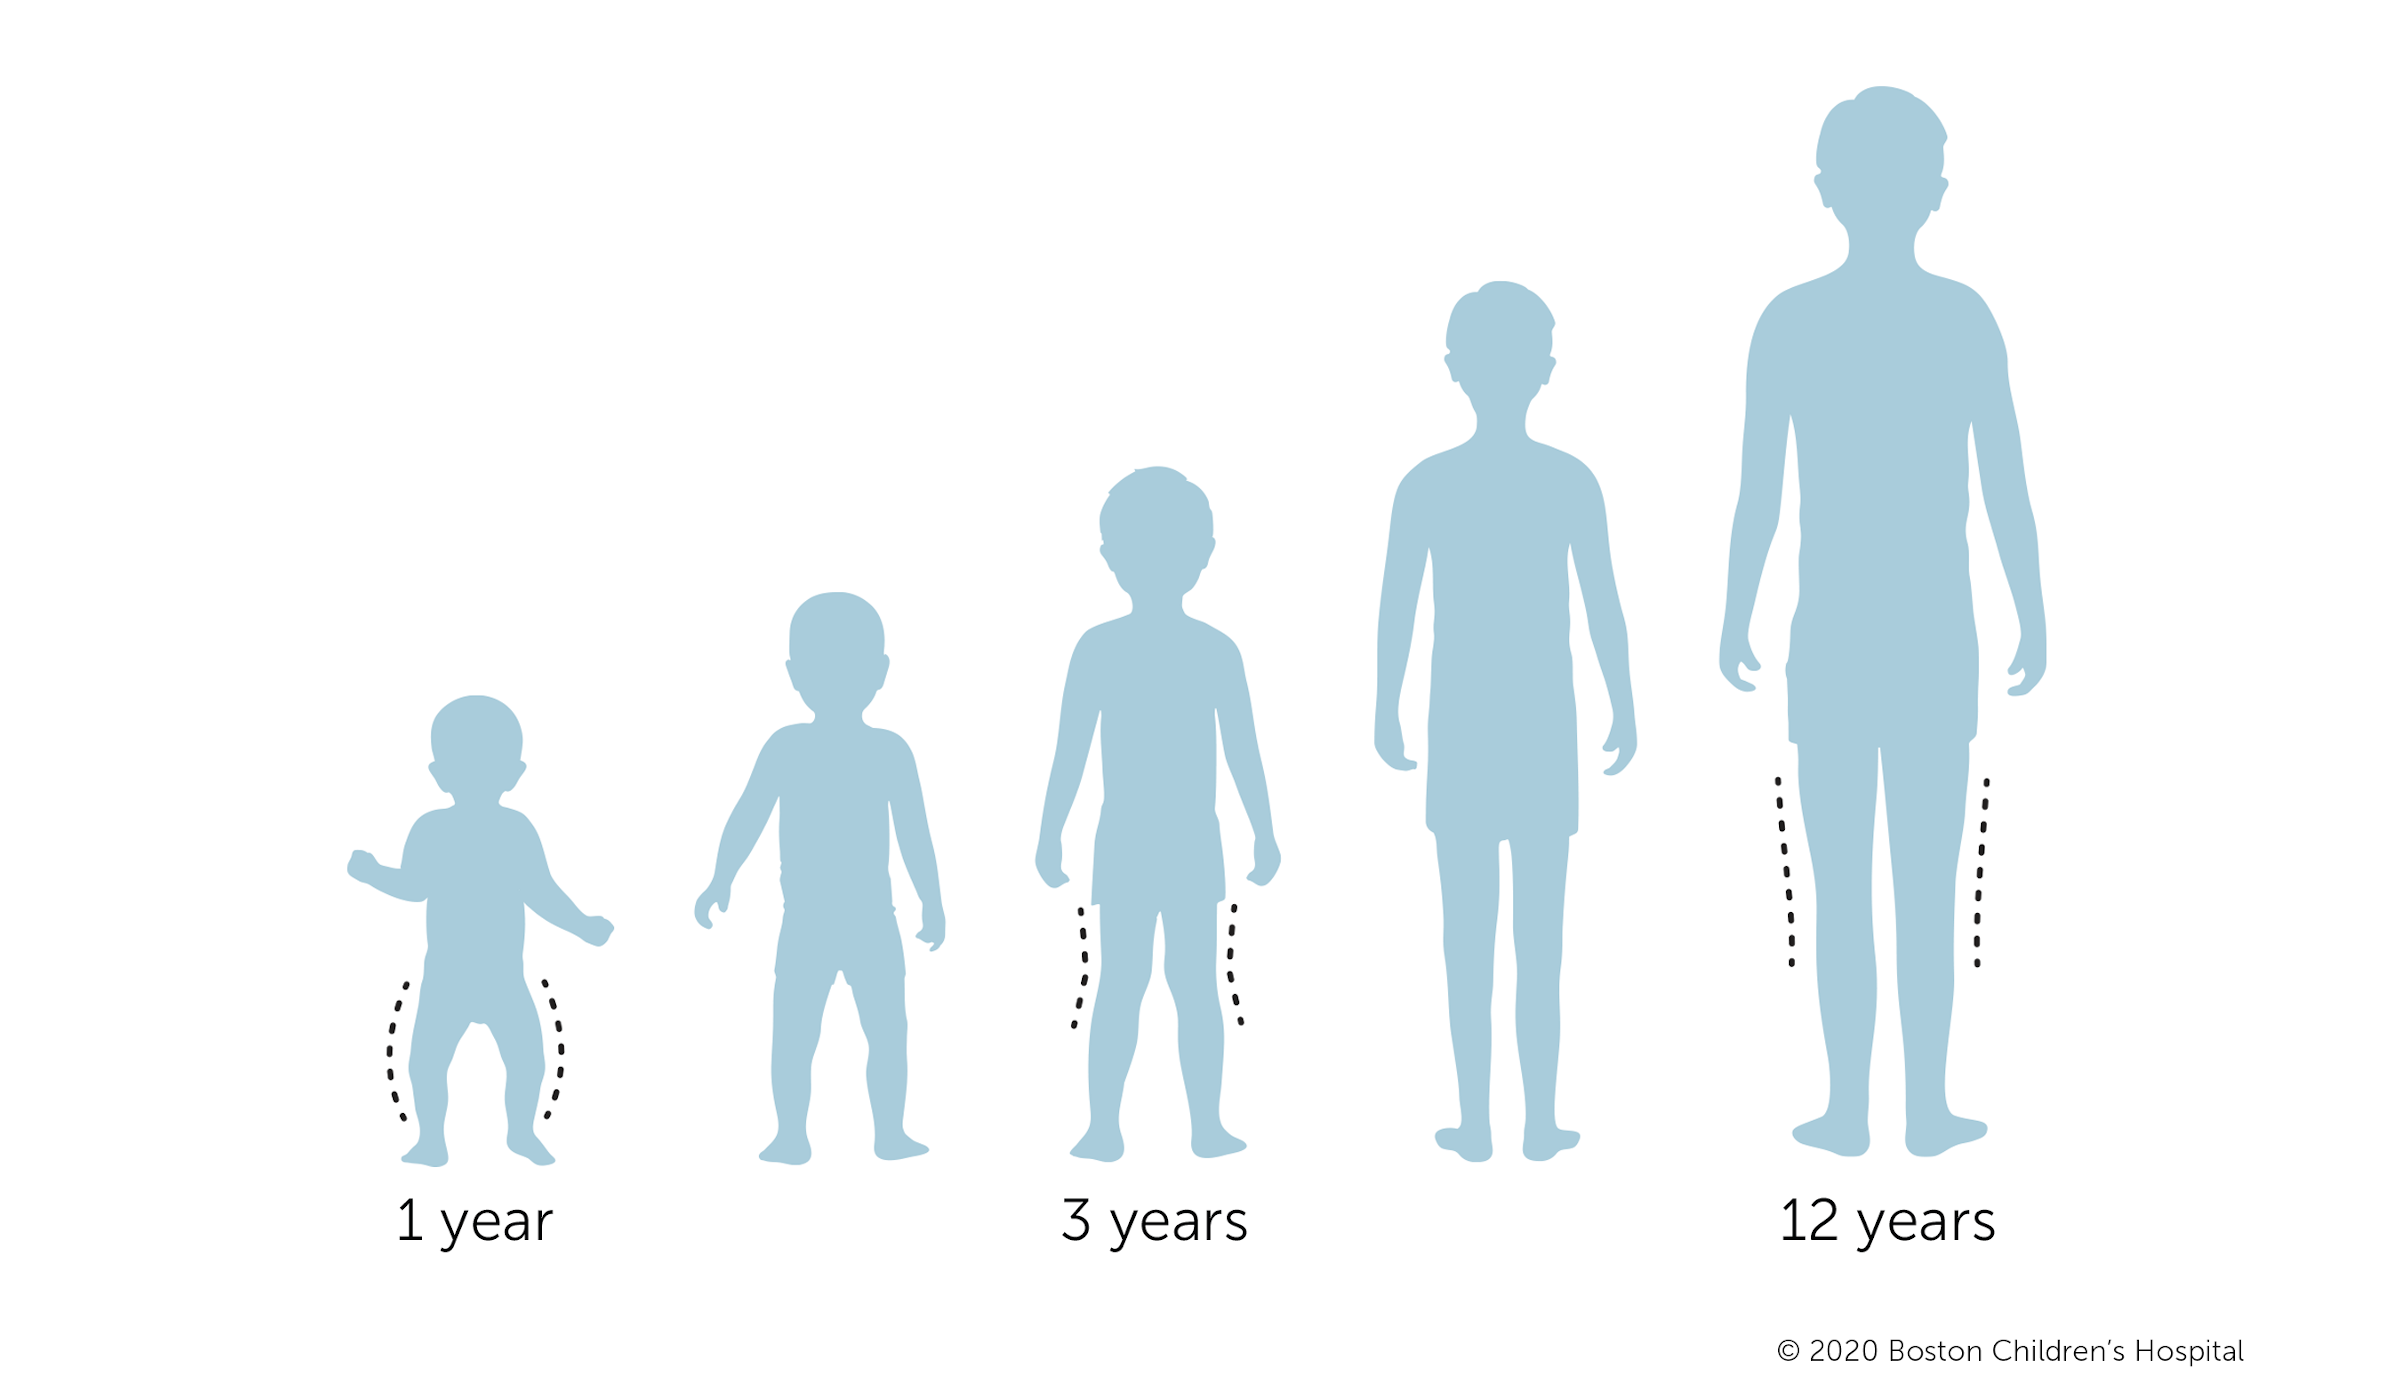

Many children go through stages of bowlegs and knock knees in their early years. As their legs grow and become stronger, the vast majority of children outgrow both bowlegs and knock knees.

- Knock knees in infants: Knock knees are not typical in infants. However, many infants have bowlegs, a condition in which both legs curve outward, up until they are about 24 months old.

- Knock knees in toddlers: Knock knees usually become apparent when a child is 2 to 3 years old. The knees may tilt increasingly inward up until about age 4 or 5.

- Knock knees in young children: Children’s legs usually become aligned by the time they are about 7. Some children continue to have knock knees into adolescence.

In most cases, children with knock knees do not need medical treatment. The most common treatment for children between 2 and 5 years old is close observation. Up to 99 percent of children with knock knees grow out of the condition by the time they turn 7. Children do not need to avoid physical activity, wear braces or special shoes, or do any special exercises.